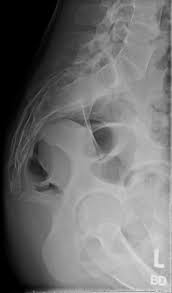

X-ray Coccyx Lateral View

Searching for a precise and affordable X-ray Coccyx Lateral View? Medifyhome provides top-quality imaging services at NABL and NABH-accredited diagnostic centers, ensuring accuracy and reliability. This specialized X-ray captures a clear side view of the coccyx (tailbone), aiding in the diagnosis of fractures, dislocations, and chronic pain conditions. It is routinely advised for people suffering from pain in the tailbone caused by injury, falling, or sustained sitting. Medifyhome has skilled radiologists who employ advanced technology to provide rapid and high-quality reports to plan effective treatment. Schedule an X-ray now by calling +919100907036 / +919100907622, and enjoy hassle-free diagnostic care with Medifyhome!